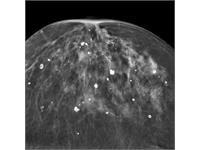

جستجو کلمه جستجو جستجو گروه بندی همه موارد مقالات » دانستنی های پزشکی زنان » پستان از تاریخ تاریخ صحیح نمی باشد. * تا تاریخ تاریخ صحیح نمی باشد. * کیست پستان چیست؟ علائم و درمان آن کیستهای پستان در واقع کیسههای پر از مایع درون بافت پستان هستند که عموماً غیر سرطانی و بیخطر هستند. این کیستها به صورت تکی یا چندتایی در سینه فرد مشا... علت ترشح از نوک پستان چیست و راههای درمان آن ترشح از نوک پستان زمانی است که از نوک یک یا هر دو بطور خود بخود و یا تحت اثر تحریک یا فشار خارجی مایع خارج شود که دلیل این ترشح همواره و الزاما نشانه ... آبسه پستان چیست؟ علائم و درمان آن آبسه پستانی که به آن ماستیت نیز گفته میشود از دیرباز یکی از مشکلات شایع مرتبط با پستانها بوده است که در بعضی از افراد در نوک پستان ظاهر شده است و هم... کلسیفیکاسیون پستان چیست و چگونه درمان میشود؟ کلسیفیکاسیون پستان رسوب کلسیم در بافت پستانی است. شامل دو نوع میکرو کلسیفیکاسیون و ماکرو کلسیفیکاسیون میشود و عمدتا غیر سرطانی و خوش خیم است. درد پستان درد پستان شایعترین شکایت در میان خانمها میباشد. این درد ممکن است در یکی یا هر دو پستان و یا زیر بغلها (اگزیلا) حس شود. اغلب این درد بصورت سنگینی و... خودآزمایی پستان چگونه است در سالهای اخیر سرطان پستان رو به افزایش گداشته است و روز به روز تعداد بیشتری از خانمها مبتلا به این نوع سرطان میشوند و به همین علت عمر آنها کوتاه م... پاپیلومای درون مجرایی چیست؟ پاپیلوما درون مجرایی یکی از انواع پاپیلوماها است که در درون مجرای شیری پستان ایجاد میشود و دارای دو نوع انفرادی و چند گانه میباشد که هر کدام دارای ن... نکروز چربی سینه چیست؟ علل ایجاد و راههای درمان آن نکروز چربی یکی از عارضههای مربوط به بافتهای مختلف بدن از جمله بافت پستان است که در بعضی از افراد دیده میشود و دلیل آن اختلال در یک آنزیم چربی میبا... همه چیز درباره ژنیکوماستی (علل ایجاد، تشخیص و درمان) بزرگ شدن سینه در مردان و پسران یا ژنتیکوماستی عارضهای است که بر اثر عوامل مختلفی ایجاد میشود. در ادامه این مطلب قصد داریم در خصوص این عارضه، علائم و... تومور فیلوئیدس چیست؟ علائم و درمان آن تومور فیلوئیدس جزء تومورهای نادر پستانی بوده واغلب در دهه 30 و 40 سن خانمها در پستان ایجاد میشود ولی در هر حال در هر سنی ممکن است بوجود آید. این توم... در مورد سرطان پستان در آقایان بیشتر بدانید آیا مردها هم سرطان سینه میگیرند؟ سوالی که بسیاری از آقایان پس از مراجعه به پزشک برای درمان بیماری خود میپرسند. در پاسخ به این سوال باید گفت اگر چه ش... انواع جراحیهای سرطان پستان جراحی سرطان پستان به دو روش ( Mastectomy) ماستکتومی و (Lumpectomy) لامپکتومی انجام میشود. تغییرات فیبروکیستیک چیست؟ بیماری تغییرات فیبروکیستیک پستان در واقع تجمع توده های غیر سرطانی و خوش خیم در بافت پستان است. فیبروکیستیک عموماً خطرناک و کشنده نیست. آیا در دوره بارداری میتوان ماموگرافی انجام داد؟ گاهی در دوره بارداری به منظور تشخیص سرطان پستان ماموگرافی انجام میشود. برای محافظت جنین از اشعه بهتر است از محافظ سربی برای پوشش استفاده شود. عمل جراحی بازسازی پستان چیست؟ طی بازسازی پستان با استفاده از عمل جراحی، پستانی با فرم و شکل جدید برای بیمار ایجاد میشود. بازسازی ممکن است پس از برداشتن همه پستان (ماستکتومی) و ی... آنچه خوب است در مورد سرطان پستان(سینه) بدانیم.(بخش اول) پستان شایعترین مکان برای ایجاد سرطان در بدن یک خانم میباشد. شیوع سرطان پستان در 50 ساله اخیر افزایش آماری قابل ملاحظهایی یافته است.در حدود 12% خانم... آنچه خوب است در مورد سرطان پستان(سینه) بدانیم.(بخش دوم) پستان شایعترین مکان برای ایجاد سرطان در بدن یک خانم میباشد. از این رو آیا تغذیه سالم میتواند شانس ابتلا به سرطان سینه را کاهش دهد؟ و آیا سیگار کشید... نمونه برداری پستان یا بیوپسی چیست؟ و انواع آن بیوپسی پستان چیست و چه کاربردهایی دارد؟ آیا نمونه برداری پستان دردناک است؟ چه مواقعی بیوپسی پستان توصیه میشود و چه مراکزی انجام میدهند؟ سونوگرافی پستان : آنچه باید پیش از سونوگرافی سینه یا پستان بدانید سونوگرافی پستان یا سونوگرافی سینه ، نوعی تصویر برداری با روش التراسوند، با هدف شناسایی توده های احتمالی موجود در بافت سینه است. تعریف پستان(BREAST ) آناتومی و بیماریهای مربوط به سینه در حال حاضر بر اساس آمارها به نظر میرسد سرطان پستان در خانمها، مهمترین عامل مرگ و میر ناشی از سرطان میباشد. آدنوزیس (Adenosis) چیست؟/ علائم و درمان آن آدنوزیس تودههای مدور کوچک و گاهی قابل لمس میباشد که بر اثر بزرگ شدن لبولهای پستان ایجاد میشوند. اگر این توده ها در محل جای زخم ناشی از عمل جراحی (... فیبروآدنوم چیست؟ علائم و درمان آن فیبروآدنوم شایعترین تودههای پستانی میباشند که سرطانی نیستند. فیبروآدنومها معمولا به تودههای بدون درد، متحرک با قوام لاستیکی در پستان گفته میشود ... چگونگی درمان ماستیت یا عفونت پستان ماستیت التهاب پستان است که باعث قرمزی، درد، احساس گرما و تورم در پستان میشود. ماستیت در شیردهی و غیر شیر دهی چیست؟ و ماستیت چگونه درمان میشود؟